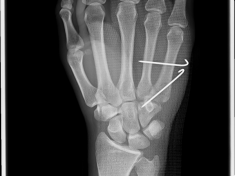

Röntgenbilder